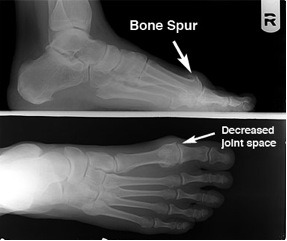

Diagnosis of hallux limitus is made by both physical examination of your foot and by x-ray examination. There is a commonly mild swelling and bony prominence associated with the first metatarso – phalangeal joint behind the big toe.

X-ray examination of the foot will reveal the true severity of the condition. It will allow the physician to evaluate the joint for bone spurs, decrease in joint space, flattening of joint surfaces, and loose bodies in the joint. X-rays can also reveal the causes of hallux limitus such as an elongated or elevated first metatarsal.